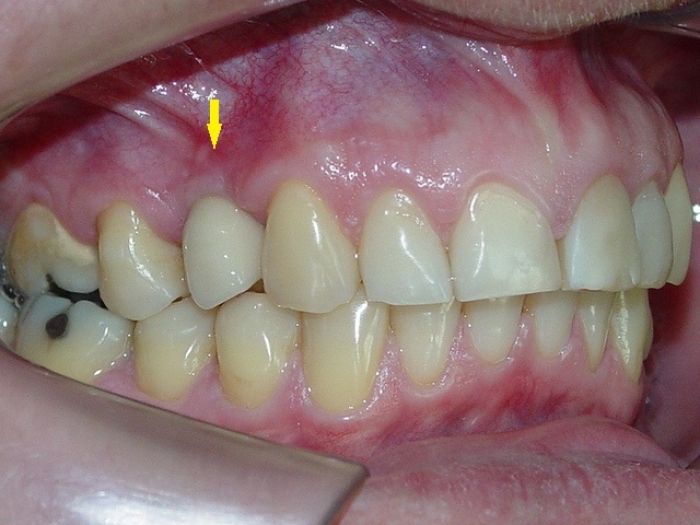

Rx e imagem da prótese fixa em porcelana sobre implante